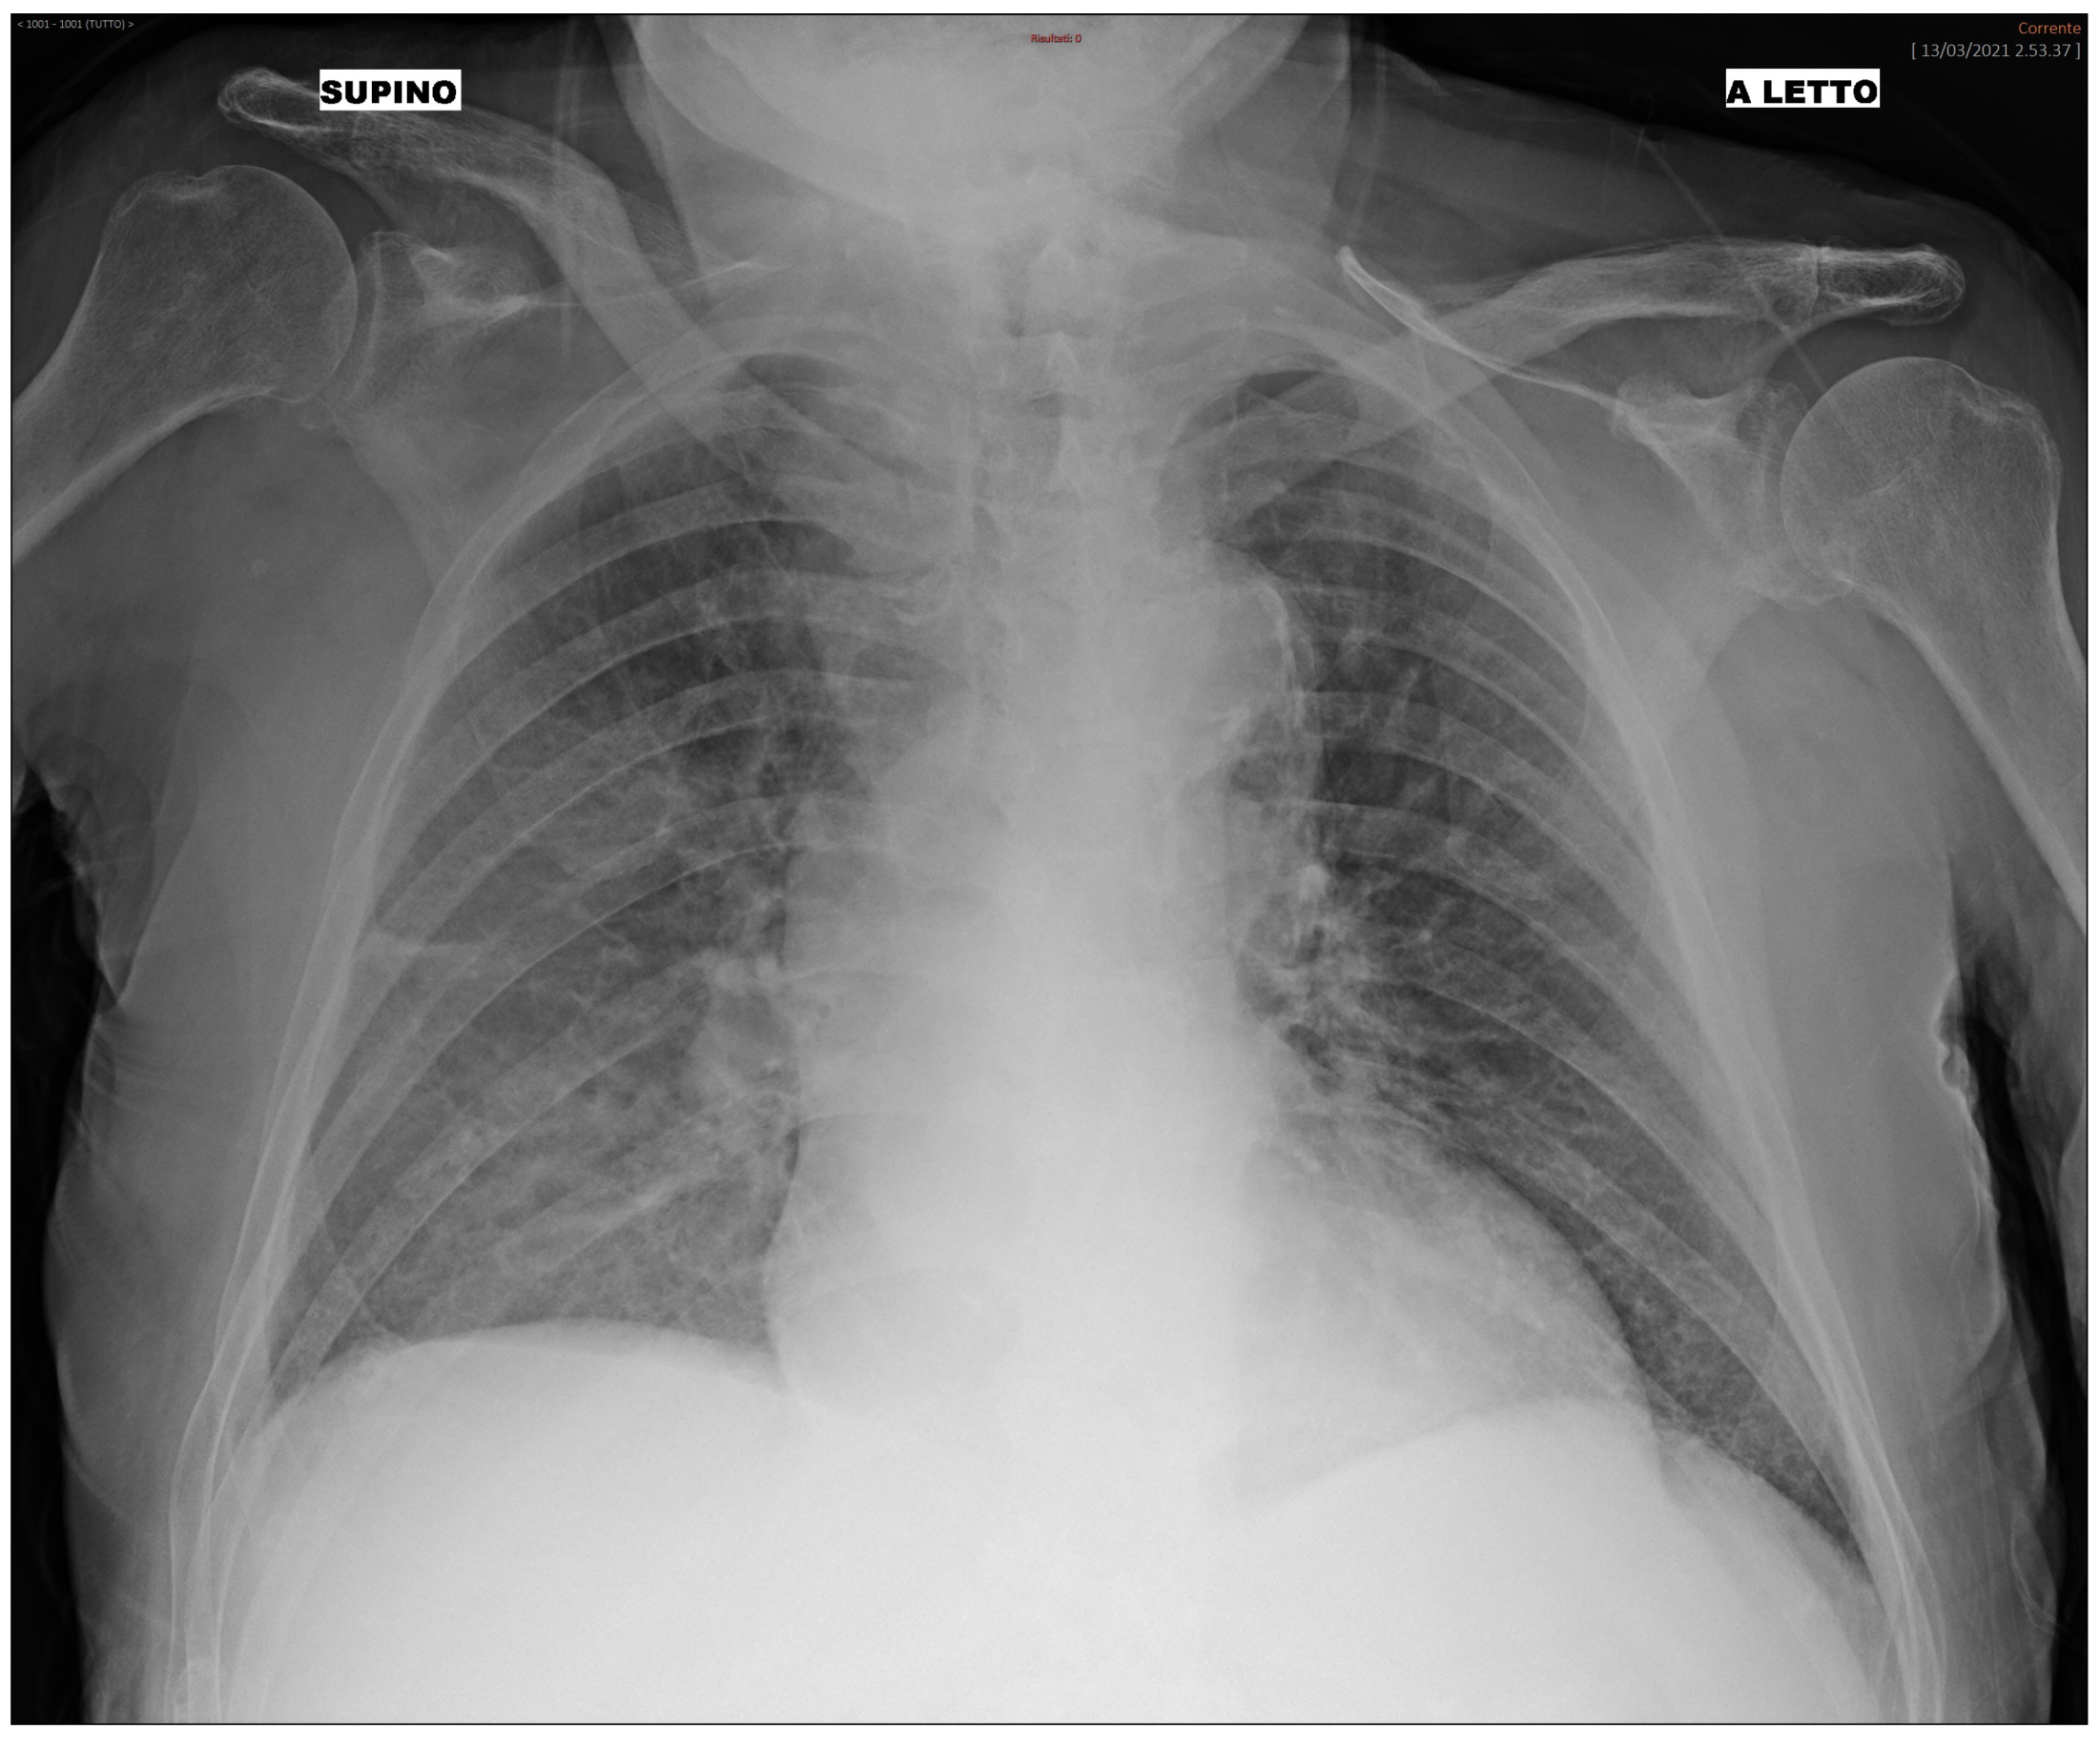

We additionally analyzed the BN and RF performance and their misclassification errors in light of prognostic outcomes that were collected after the initial diagnosis for each patient of the third wave set. In summary, each patient included in the study (both treated at home or in hospital), underwent follow-up, and clinicians recorded the outcomes after some time from the initial diagnosis. Patients with mild outcomes were those not hospitalized or hospitalized without the need for ventilation support. Patients with moderate outcomes were hospitalized with airway pressure device support, while severe patients were those hospitalized with invasive ventilatory support or who were deceased. We analyzed misclassification errors by the BN, and we correlated it with the follow-up outcome. We found that, for False Positive patients (i.e., patients predicted “hospital” where in fact they were treated at home at the beginning), a higher percentage of severe and moderate patients were detected. In False Negative patients, most of them had a mild outcome. For instance, we present the case of a 92-year-old male patient who underwent triage during the third wave. The patient did not present with cough, dyspnea, or any significant functional impairment. The CXR image of the patient is depicted in Figure 3 and shows alteration mainly in the right lung. Both the BN and the RF incorrectly predicted the “Hospital” class, while the patient was not initially hospitalized. However, 7 days after the first triage, the patient returned to the ER with worsened symptoms and was subsequently hospitalized. This serves as an example of where the ML prediction contradicts the ground truth (i.e., the medical decision during the first triage). Nonetheless, the progression of the disease, leading to a delayed hospitalization, implies that the ML prediction might have been correct, suggesting an alternative scenario to clinicians at the time of the initial triage of the patient. The availability of the prediction from the algorithm during the first triage might suggest more caution to the clinician in weighing the chest X-ray with other factors (such as the age of the patient) and leading to more safe management even when a functional impairment is not yet present.

Figure 3.

Bedside CXR image of a 92-year-old patient classified by the ML as “Hospital”.